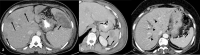

The purpose is to discuss abdominal tuberculosis mimicking malignancy involving the abdominal viscera. TB of the abdominal viscera is common, especially in countries where tuberculosis is endemic and in pockets of non-endemic countries. Diagnosis is challenging as clinical presentations are often non-specific. Tissue sampling may be necessary for definitive diagnosis. Awareness of the early and late disease imaging appearances of abdominal tuberculosis involving the viscera that can mimic malignancy can aid detecting TB, providing a differential diagnosis, assessing extent of spread, guiding biopsy, and evaluating response.